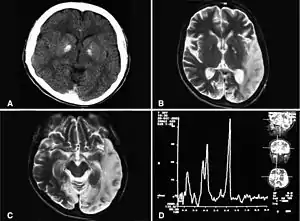

| کلسیفیکاسیون عقدههای قاعدهای، آتروفی مخچه، افزایش لاکتات؛ تصاویر سیتی اسکن یک فرد مبتلا به سندرم ملاس | |